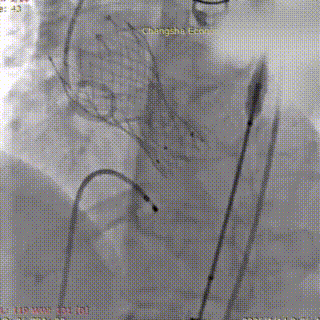

术中影像:

输送系统和DL23瓣膜到达释放位置定位造影

瓣膜释放至三分之二处

瓣膜开始工作,造影评估,位置良好

瓣膜完全释放,造影评估,瓣膜位置良好

在调整血管活性药物至更稳定剂量、并做好所有应急准备后,再次进行球囊预扩张。此次扩张过程顺利,未再发生严重循环波动。造影证实球囊位置准确,无腰征,扩张过程顺利,无瓣周漏加重及冠脉阻塞征象。确定VenusA Deluxe DL 23 mm 自膨式经导管主动脉可回收瓣膜系统,经超硬导丝送瓣膜输送系统平稳通过股动脉、髂动脉及腹主动脉,无阻力送至主动脉瓣环位置。经多角度造影确认瓣膜支架标记点与主动脉瓣环、冠脉开口相对位置。最终,将瓣膜稳定释放并锚定于标准解剖位置。造影及TEE显示:人工瓣膜支架展开形态良好,无显著瓣周漏;主动脉瓣前向血流显著改善,平均压差大幅下降;左右冠状动脉显影清晰,患者血流动力学指标立时改善。